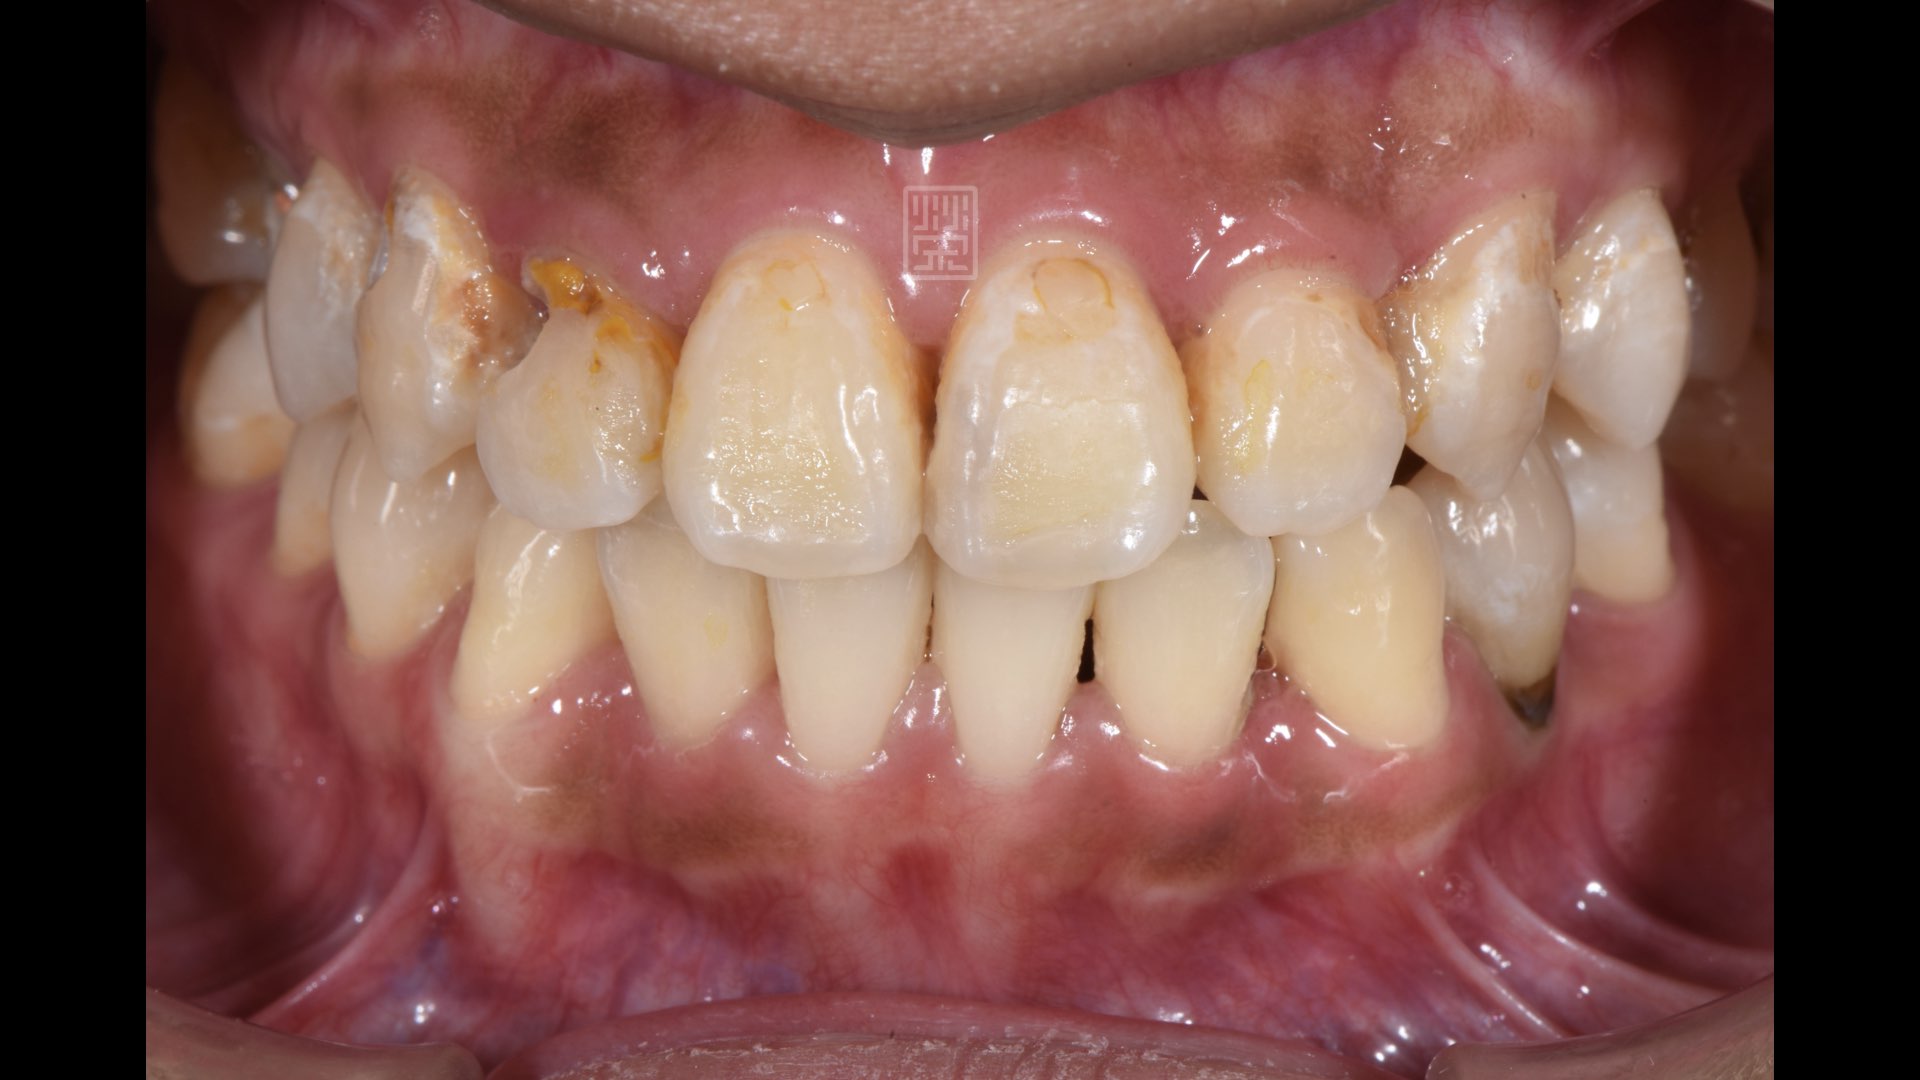

也就是因為這樣,長期對於牙科很懼怕,除非到最後一刻,不然絕不踏進牙醫診所一步,這也造成許多深及牙根的蛀牙甚至牙齒斷裂,已經嚴重造成飲食問題了。

經過診斷後,發現有牙髓神經發炎、深及牙根蛀牙、牙齒斷裂後的殘根、矯正後殘餘固定器的樹脂;藉由奈米樹脂、全瓷冠、植牙恢復功能與美觀。

牙齒蛀牙造成牙髓神經發炎

牙齒明顯蛀洞